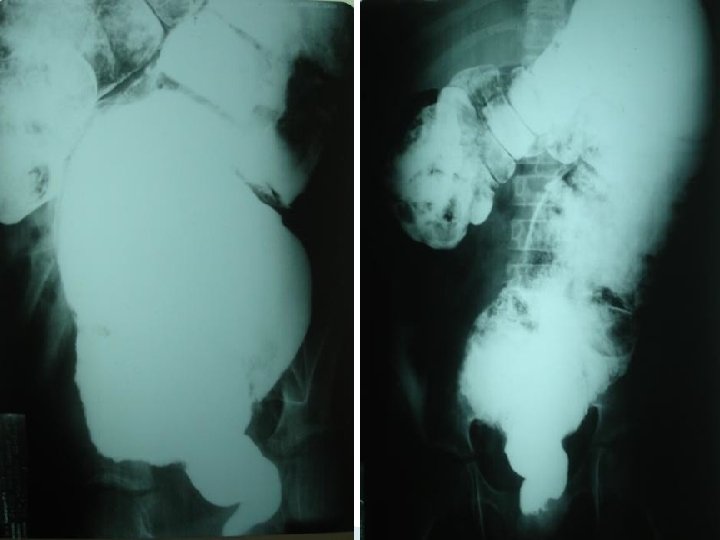

Rx pós operatório

Megacólon congênito Doença de Hirschsprung Diagnóstico radiológico: A radiografia simples de abdome evidencia distensão de alças com ausência de ar nos segmentos distais, na maioria dos casos. O enema baritado, obrigatoriamente realizado sem preparo de colo, e com as radiografias tardias de 24, 48, 72 e até 96 horas, classicamente revela imagem de “cone de transição”, geralmente ao nível do retossigmóide, que separa o segmento espástico de intestino agangliônico da zona dilatada a montante;

Íleo Meconial Diagnóstico Radiológico: Distensão de alças intestinais; Nível líquido só no estômago; Imagem de mecônio misturado com ar, simulando “vidro moído” – sinal de Neuhauser; O clister opaco – revela um microcolon;